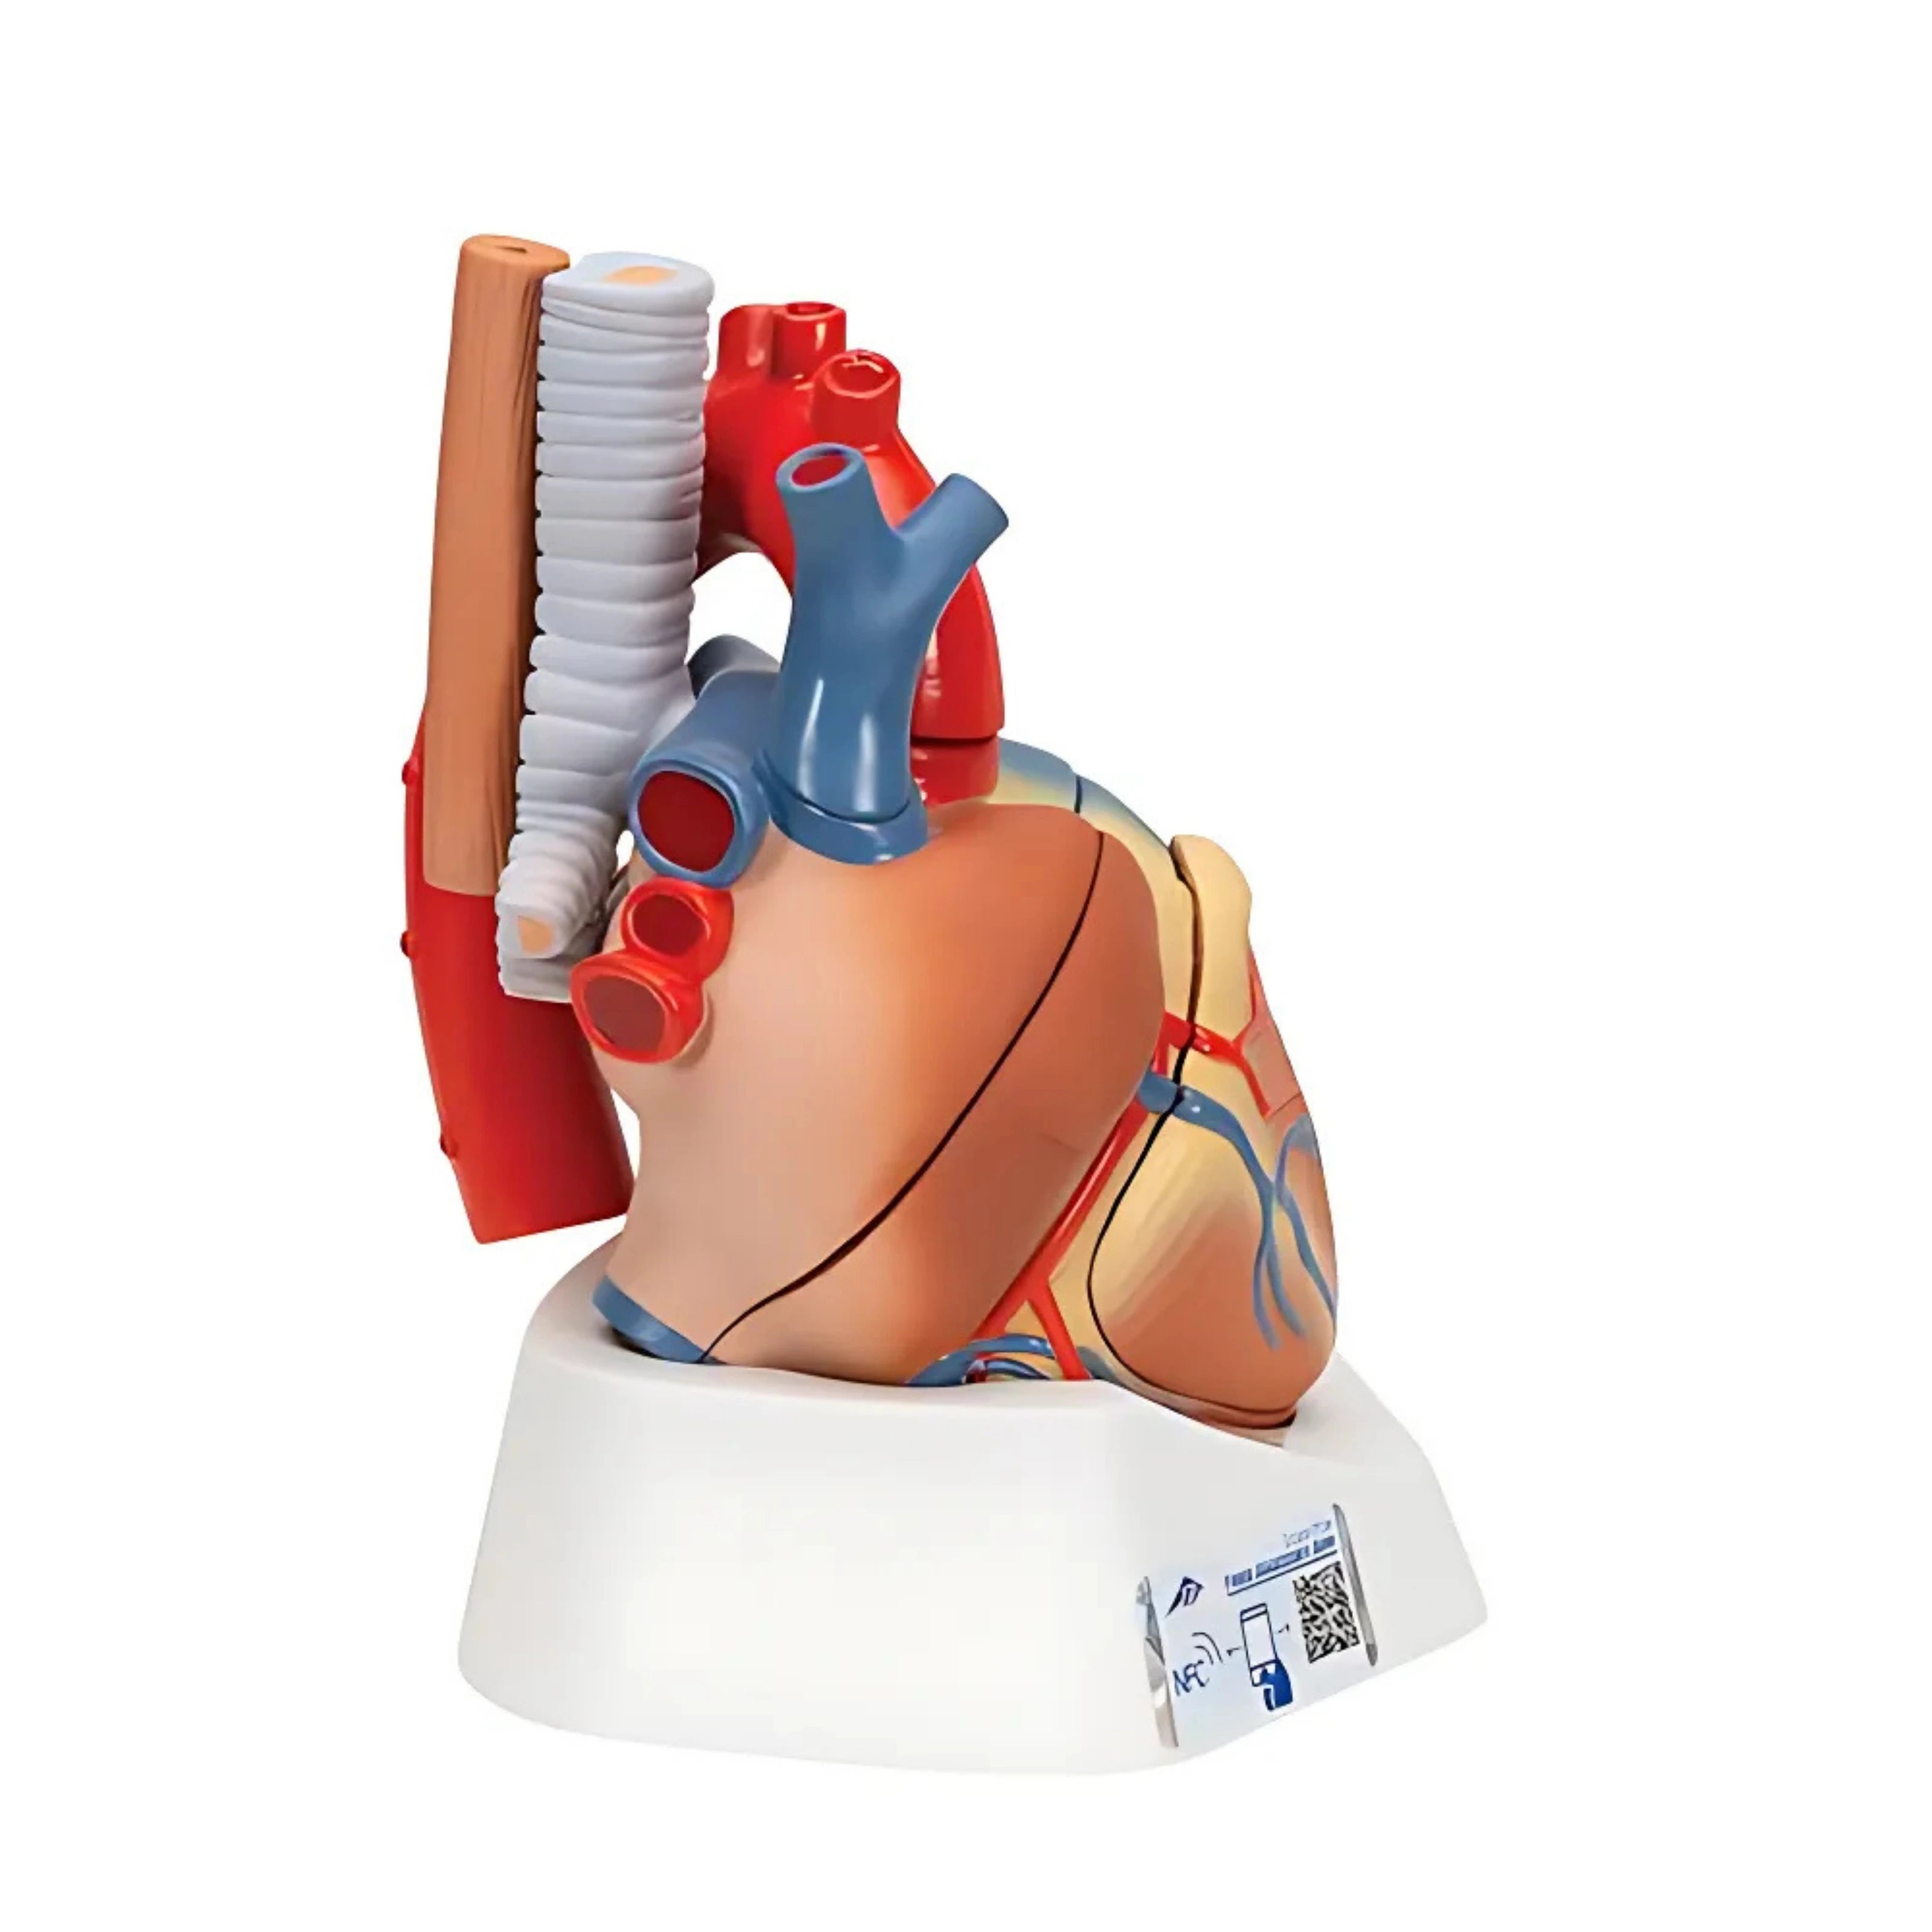

Órganos internos: corazón, pulmones, hígado, riñones, sistema digestivo y reproductivo.

Modelos especializados: cardiología, neurología, ginecología, ortopedia y más.